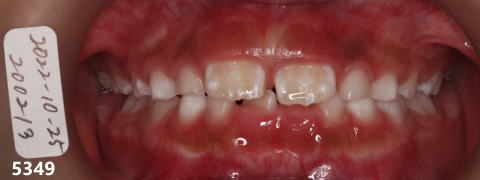

2022年10月25日

初診:咬合が低い

乳歯の臼歯にレジンを

のせて咬合を上げる。